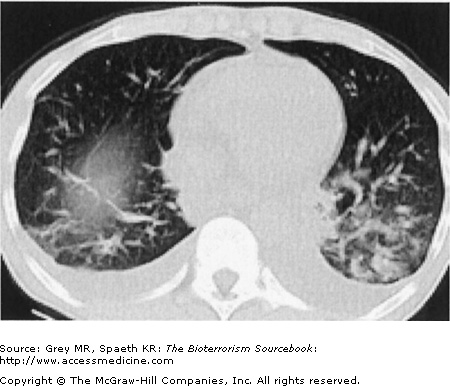

Inhalational anthrax is characterized by a series of radiographic and tomographic changes that can aid greatly in diagnosis. Radiographs provide critical diagnostic information many hours or even days before blood or sputum cultures can turn positive. These changes, when presenting late, indicate a poor prognosis. Computed tomography (CT) taken of the post-September 11 anthrax patients also showed characteristic abnormalities that have substantial diagnostic value. Initial CTs in virtually all of the post-September 11 inhalational anthrax cases were markedly abnormal and had an unusual combination of findings of enlarged hyperattenuating mediastinal and hilar lymph nodes, diffuse mediastinal fat edema, peribronchial thickening, and pleural effusions. Given the rarity of inhalational anthrax in the modern era, this terrorist attack provided valuable information for the presentation of anthrax in the era of CT scans. The findings corroborate the classic chest radiograph findings. CT scans are now considered a standard diagnostic tool for inhalational anthrax. These key radiographic findings are summarized in Table 14–2 (see also Figs. 14–5, 14–6, 14–7, and 14–8).